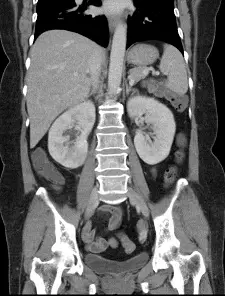

28.電腦斷層檢查如下圖,下列敘述何者最適當?

本題測驗電腦斷層(CT)影像後處理技術與人體解剖切面的基本辨識能力。醫事放射師在執行 CT 檢查後,常需要利用原始的軸狀面(Axial)體積數據,進行不同的影像後處理,以提供臨床醫師更多視角的診斷資訊。最常見的技術包含多平面重組(MPR)、容積渲染(VR)、最大值投射(MIP)等,且必須熟悉冠狀面(Coronal)、矢狀面(Sagittal)與軸狀面(Axial)的解剖特徵。

- 解剖構造辨識:

- 影像上方兩側可見:患者右側為大面積的肝臟 (Liver),左側為脾臟 (Spleen)。

- 影像中段兩側:可見一對明顯的腎臟 (Kidneys),並清楚顯示皮質與髓質的差異。

- 影像正中央:為一節一節的脊椎骨 (Vertebral column)。

- 影像下方:可見骨盆腔 (Pelvis) 與兩側的髖關節 (Hip joints)。

- 切面判定 (Plane):

- 能夠同時觀察到人體的「左與右」以及「上與下」的相對關係,並呈現出面對患者正面的視角,此為冠狀面 (Coronal plane)。

- 後處理技術判定 (Reconstruction Technique):

- 該影像呈現標準的 2D 灰階斷層畫面,依賴不同組織的